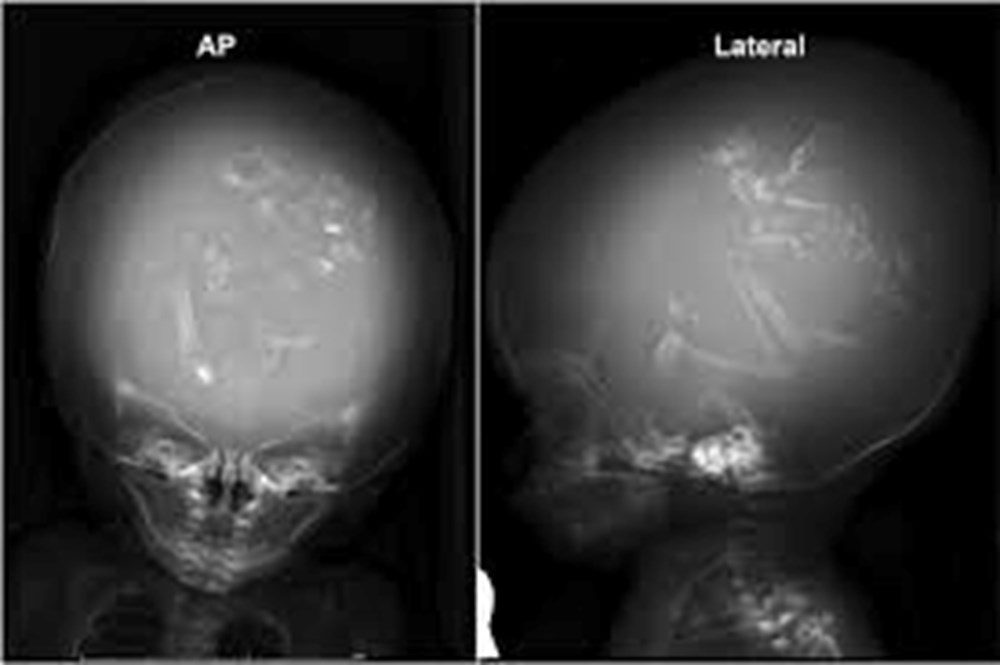

Yeni bir araştırmaya göre, Çin’de doktorlar bir yaşındaki bir çocuğun beyninde ‘doğmamış ikizinin fetüsünü’ buldu. Neurology dergisinde yayınlanan çalışmada, çocuğun motor fonksiyonlarında sorunlar yaşaması ve kafasının büyümesi üzerine ebeveynleri tarafından hastaneye getirildiği ortaya çıktı. Şangay’daki doktorlar, doğmamış ikizin fetüsünün çocuğun beyninde geliştiğini tespit etti. Çalışmanın yazarları, “Motor becerilerinde gecikmesi ve genişlemiş baş çevresi olan 1 yaşındaki bir kız çocuğunda malforme olmuş monokoryonik diamniyotik ikiz olan intraventriküler fetüs içinde fetüs (fetus-in-fetu) tespit edildi.” denildi.

Bununla birlikte fetüs içinde fetüs vakaları ikiz gebeliğin çok erken aşamalarında, döllenmiş bir yumurta tarafından oluşturulan ve blastosist olarak adlandırılan bölünen hücre kümesinin düzgün bir şekilde ayrılamamasıyla meydana geliyor. Ardından embriyolardan biri diğeri tarafından çevreleniyor.

Diğer ikizin çoğalan hücreleri tarafından sarılan öteki fetüs gelişemiyor, ancak kan desteği aldığı için “canlı” kalıyor.  Çalışmada, “Yapışık parçalar ana fetüsün ön beynine dönüşüyor ve nöral plak katlanması sırasında diğer embriyoyu sarıyor.” ifadeleri kullanıldı.